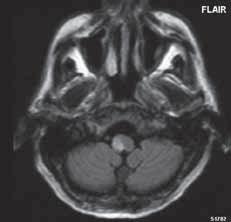

Diferenciální diagnostika

• Arachnoidální cysta v zadní jámě lební není doprovázena hypoplazií mozečku ani rozšířenou IV. komorou, ale tyto struktury mohou být tlakem cysty dislokovány. Hydrocefalus ani rozšířená zadní jáma lební nepatří do typického obrazu arachnoidální cysty v zadní jámě lební. Obsah cysty se může mírně lišit od signálu likvoru „zahuštěním proteinů“, což je důvodem zvýšené intenzity signálu v T1W obrazu, eventuálně denzity oproti likvoru v modalitě CT.

• Joubertův syndrom (molar tooth malformace): jedná se o malformaci středního mozku, charakterizovanou dysplazií vermis, mohutné horní mozečkové pedunkuly, nepřítomnosti křížení pyramid v mozkovém kmenu, často jsou další malformace CNS. Na transverzálních řezech v úrovni mozkového kmene obraz připomíná „zubní stoličku“. Pozorujeme abnormální pohyby očních bulbů, poruchy dýchání, ataxii, psychomotorickou retardaci.

• Rombencefalosynapse: spočívá v agenezi vermis, splynutí mozečkových hemisfér, pedunkulů, někdy i nn. dentates. Pozorujeme absenci vermis, spojení mozečkových hemisfér, pedunkulů, nn. dentates. Celý mozeček je zmenšený, sulci cerebelli přecházejí přes střední čáru, bez přerušení na druhou hemisféru, hydrocefalus je velmi častý. Většina jedinců umírá, přeživší nemocní mívají psychomotorickou retardaci, klinický obraz je ovlivněn dalšími supratentoriálními malformacemi, které jsou časté.

• Vrozené hypoplazie mozečku: mozečkové struktury jsou „malé“, ale není absence vermis, obvykle dědičná onemocnění.

Arachnoidální cysta Joubertův syndrom (molar tooth malformace) Hypogeneze mozečku